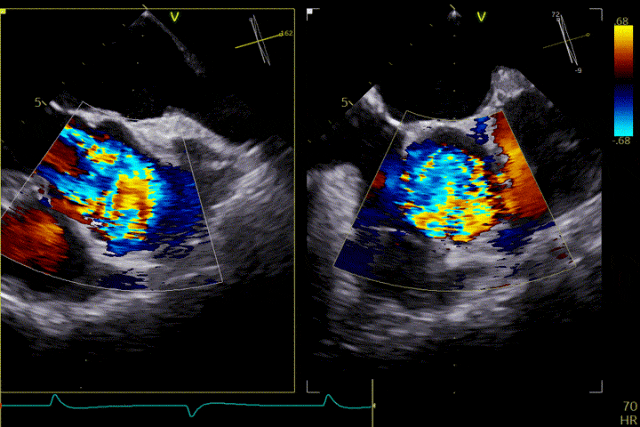

在超聲引導下,手術團隊高效且精準地完成了瓣膜的定位、釋放及功能評估。手術過程順利,夾持件入竇與定位一氣呵成,三枚夾持件的釋放與錨定位置均與術前評估完全一致,器械操作時間約5分鐘。術中超聲評估顯示無瓣周漏,血流動力學表現穩定,手術順利完成。

患者主動脈瓣重度反流得到糾正,術後無反流、無瓣周漏。術後心臟超聲顯示人工生物瓣啟閉功能良好,平均跨瓣壓差2 mmHg,血流速度正常。患者恢復情況良好,心功能較術前明顯改善。